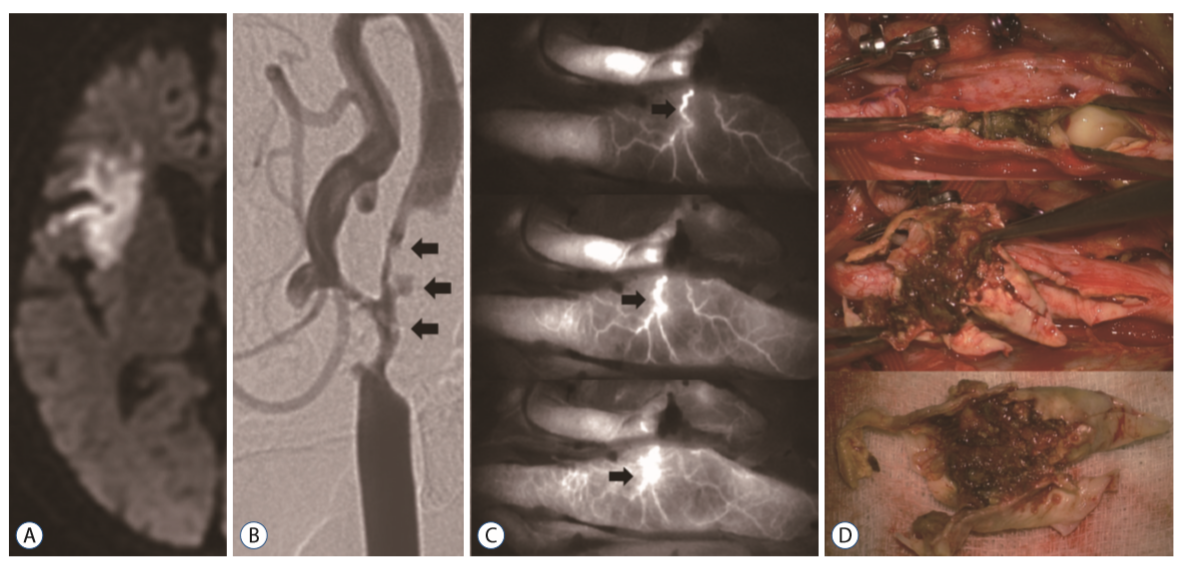

按来源,滋养血管主要可分为三种(参考下图):

内源血管滋养管(Vasa vasorum internae,VVI),直接源自于血管腔,进入血管壁中。

外源血管滋养管(Vasa vasorum externae,VVE),源自于动脉分支,之后再回来供养同一血管。

静脉向血管滋养管(Venous vasa vasorae,VVV),源自于动脉壁,但之后注入临近的静脉。

自2015年9月至2017年12月,纳入69例行CEA的患者(症状性患者,狭窄程度≥50%;无症状患者,狭窄程度≥70%)。CEA期间,在切开颈动脉之前,由一名麻醉师在进行血管造影时静脉注射ICG,分析造影结果,确定管腔狭窄情况以及滋养血管类型。

所有患者均观察到了滋养血管,其中外源血管滋养管(VVE)11例(16%),内源血管滋养管(VVI)57例。VVE型与颈动脉易损斑块(90.9%,p = 0.017)密切相关。与稳定斑块相比,不稳定斑块中观察到CD68染色的巨噬细胞和CD117染色的肥大细胞的频率更高。